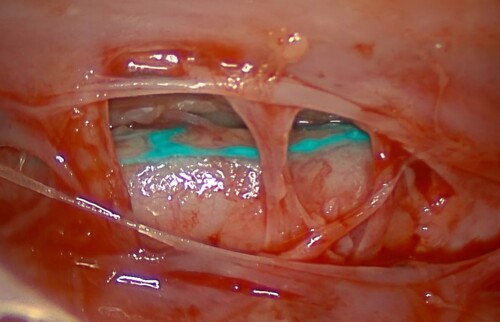

Die Pleura stellte sich in der OP, wie erwarte, stark verdickt dar, es wurde eine erhebliche Menge an chylösem abgesaugt. Der Ductus thoracicus wurde mittels NIR-Spektroskopie dargestellt. Dazu wurde in den mesenterialen Lymphknoten Indocyan­grün-Flüssigkeit injiziert, welche sich durch die Absorption von Nahinfrarotlicht durch das Gewebe cyan färbt. (Abb. 5) Dadurch könnte eine gezielte Ligatur des Ductus thoracicus durchgeführt, um den Austritt von Lymphflüssigkeit zu stoppen. Für die Perikardektomie und die Lungenlappen­resektion wurde ein minimal-invasives chirurgisches Verfahren mittels Video-assistierter Thorakoskopie (VATS) gewählt um Merlins postoperative Schmerzen und Komplikationen möglich gering zu halten. Zu guter Letzt wurde noch ein Drainagesystem in den Pleuraspalt eingelegt (Abb. 5), über diesen Pleuraport soll, wenn nötig eine postoperative Ansammlung von Flüssigkeit abgezogen werden.

Darstellung des Ductus thoracicus mittel NIR

Abb. 4 Darstellung des Ductus thoracicus mittel NIR